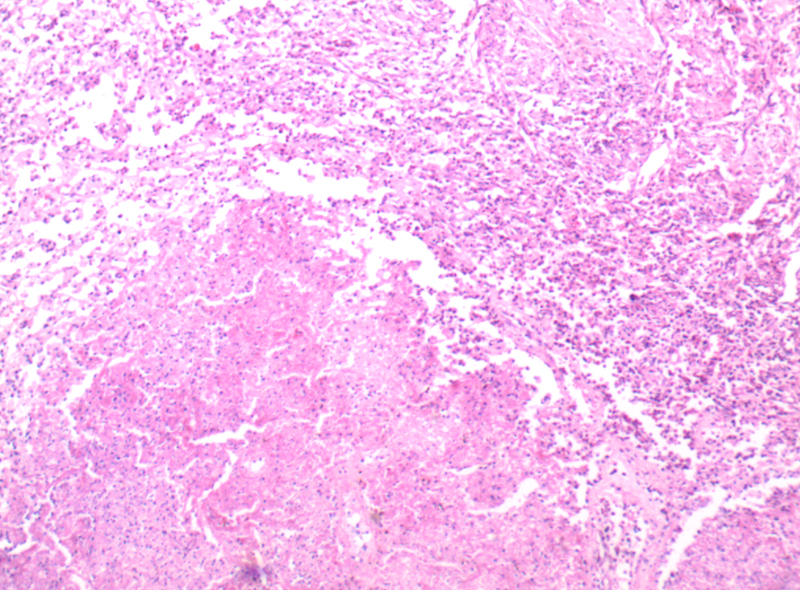

肺羊水栓塞